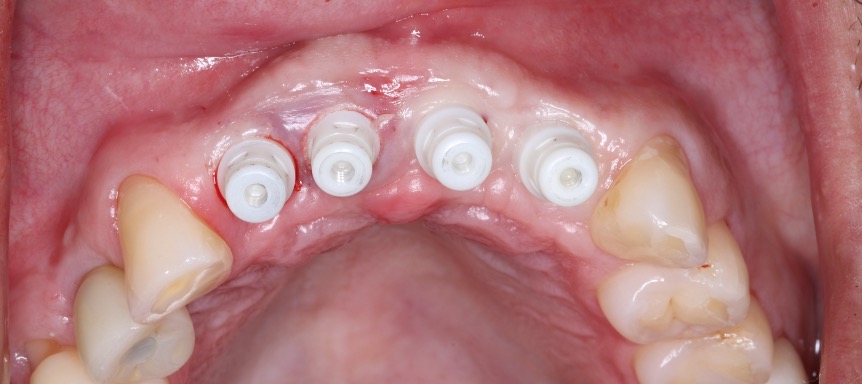

March 06, 2024Placement of four maxillary anterior implants (#7–10 region) into regenerated bone with careful three-dimensional positioning and provisionalization to support soft tissue shaping.

June 08, 2024Follow-up visit confirming implant stability, soft tissue healing, and refinement of the anterior emergence profile in preparation for final restorations.